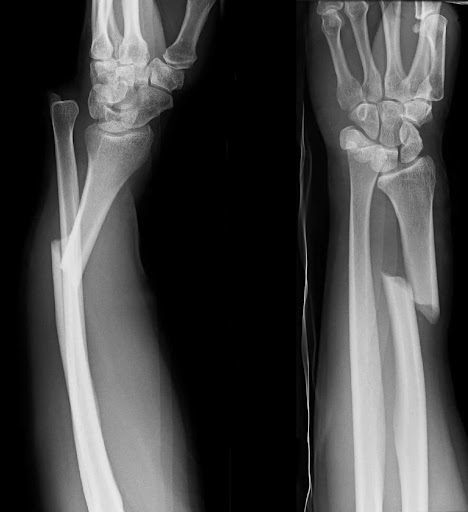

폐쇄성골절의 정의와 특징

폐쇄성골절은 골절이 발생했지만 피부가 찢어지지 않고 외부와 연결되지 않은 상태를 의미합니다. 흔히 "닫힌 골절"이라고도 표현합니다.

폐쇄성골절의 특징은 다음과 같습니다.

- 피부 손상이 없음

- 골절 부위가 외부에 노출되지 않음

- 감염 위험이 상대적으로 낮음

- 내부 출혈 및 조직 손상은 존재 가능

폐쇄성골절의 주요 특징을 정리하면 다음과 같습니다.

- 외관상 상처가 없어 초기 판단이 어려울 수 있음

- 통증, 부종, 변형으로 판단

- X-ray, CT 등 영상검사 필수

- 대부분의 일반 골절이 여기에 해당

즉, 폐쇄성골절은 "피부가 열려 있지 않은 상태"를 의미하는 분류이며, 압축골절과는 완전히 다른 기준입니다.